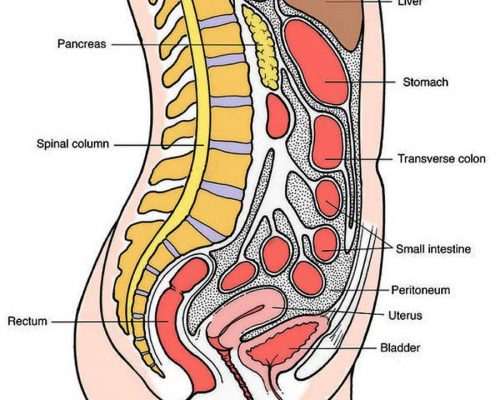

Viscero Somatic Dysfunction

When analyzed by a doctor, physical brokeness is treated by (omt) Specialists by viscero somatic dysfunction.